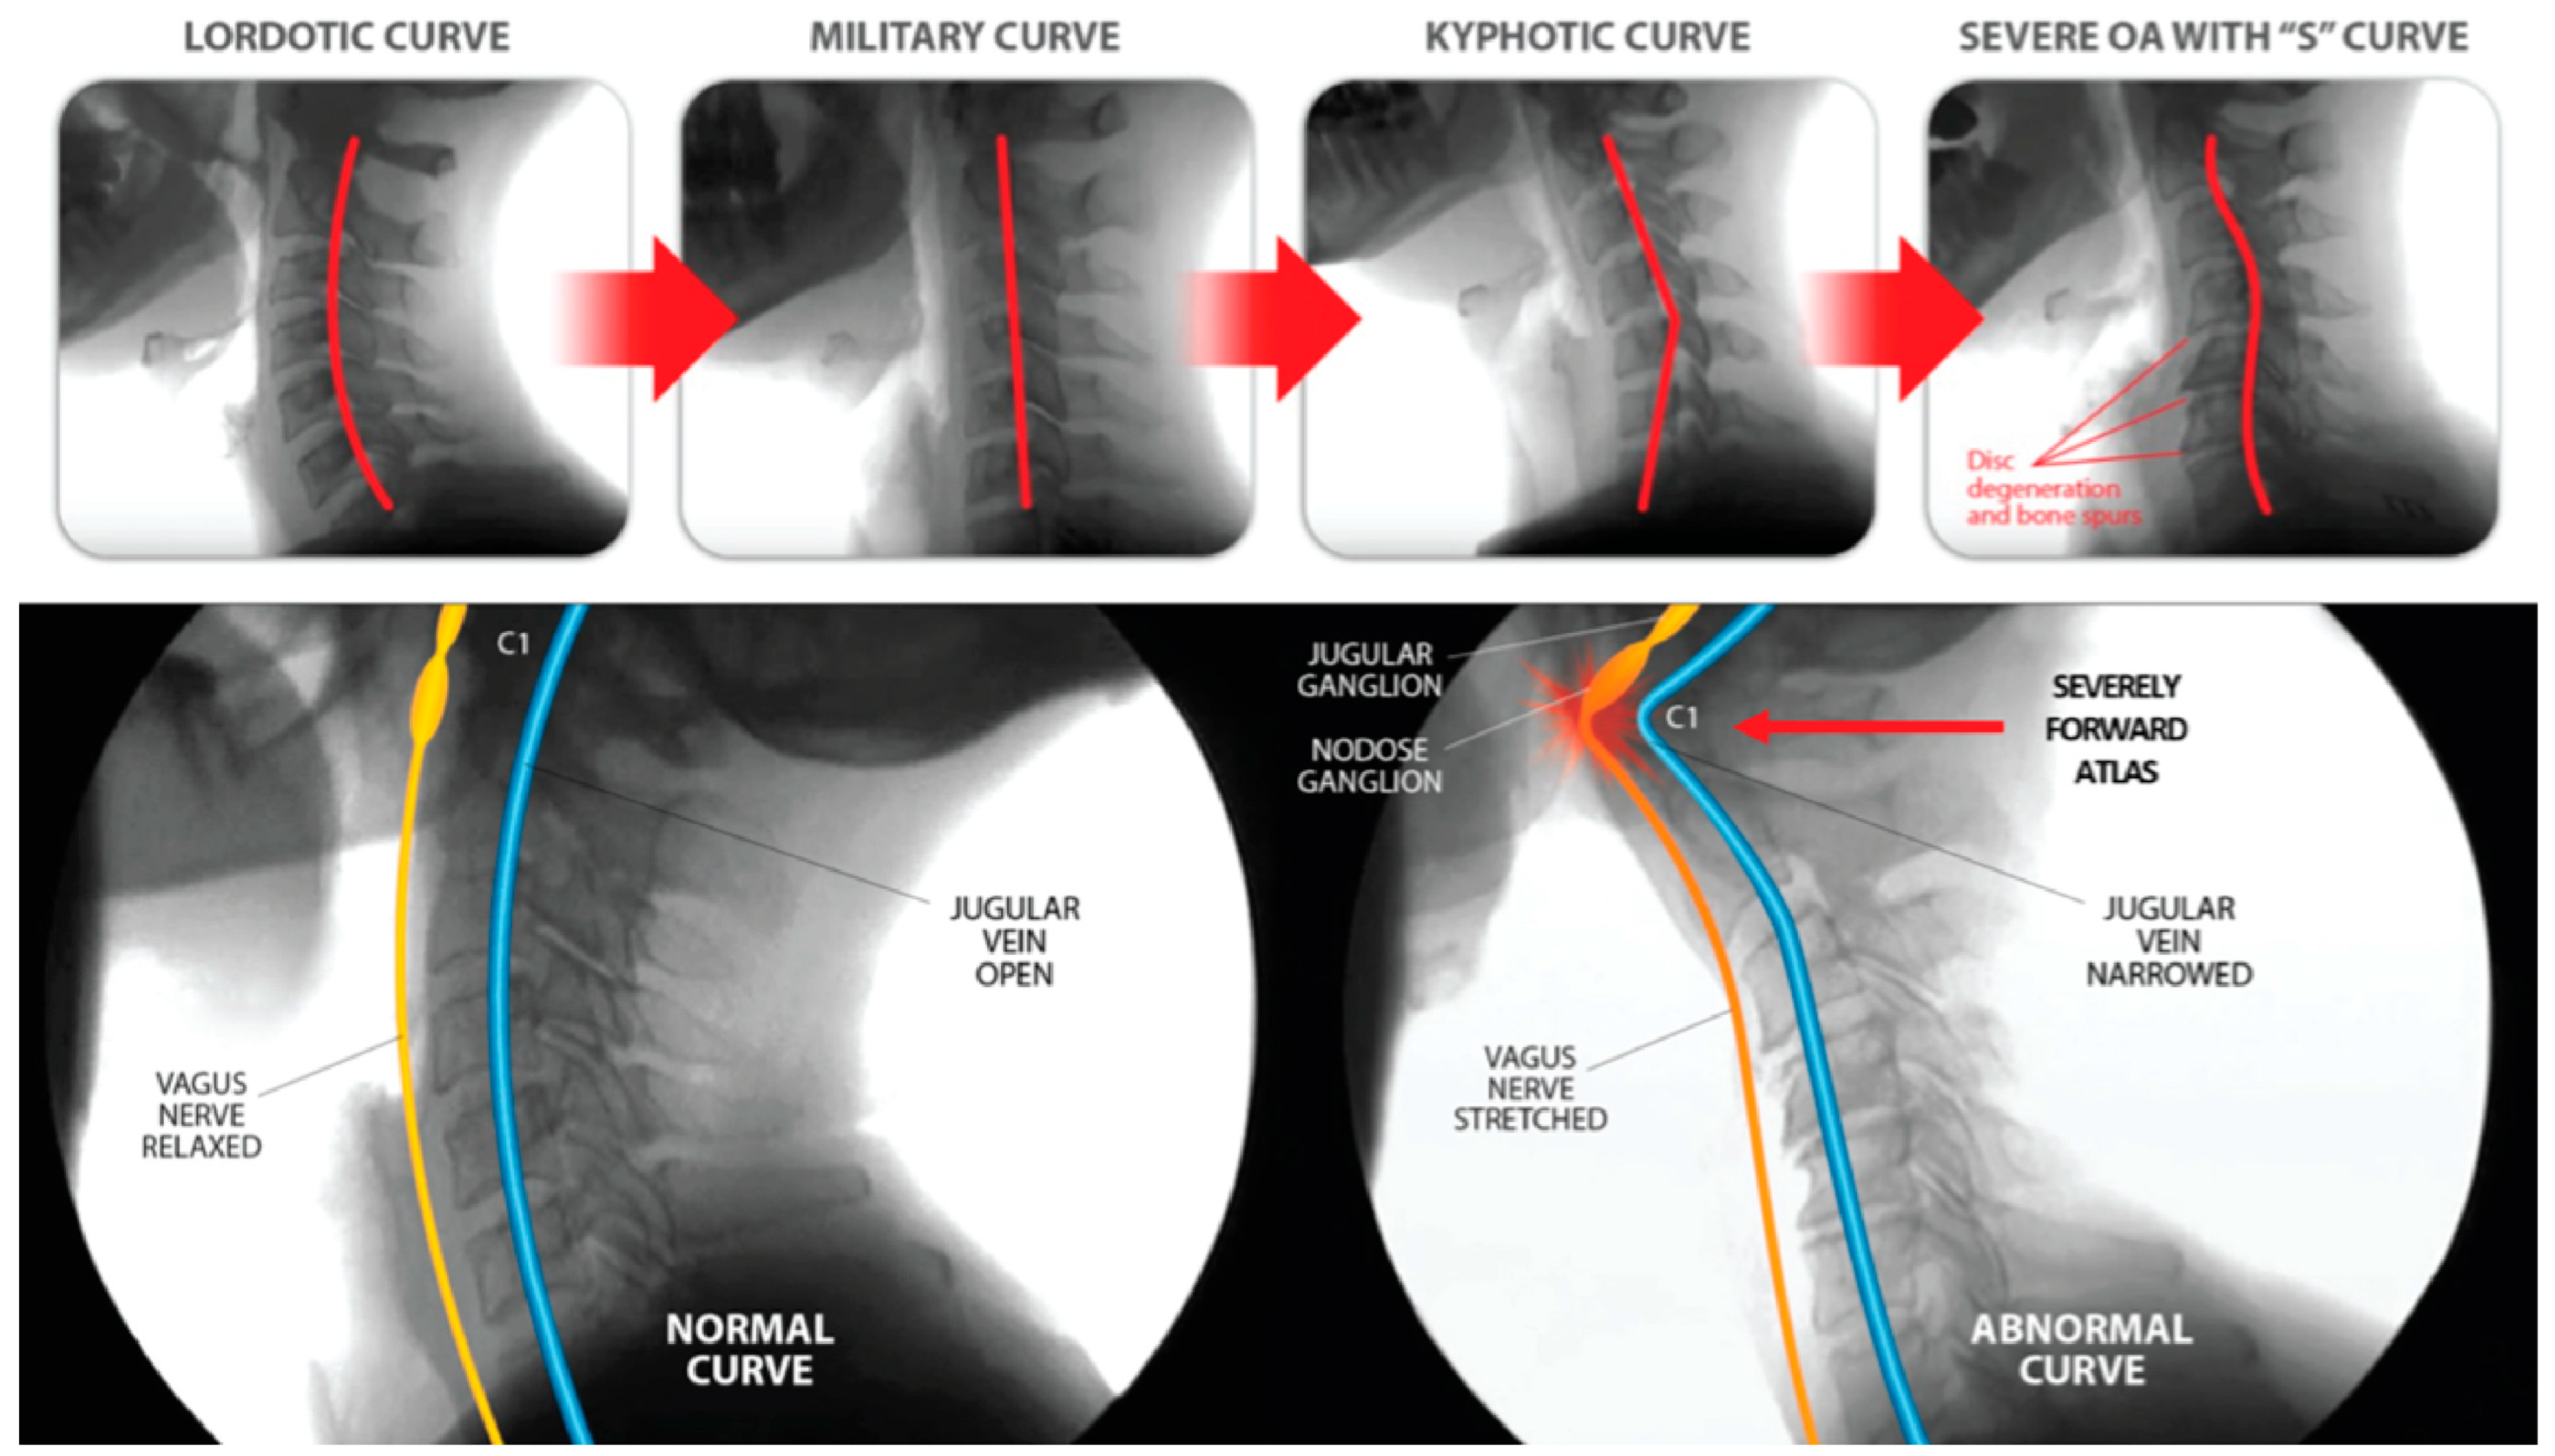

5. Cervical Lordotic Curve

3.1. Facedown/Forward Head Lifestyle and Global Increase in Visual Impairment

3.2. Facedown/Forward Head Lifestyle Leads to Ligamentous Cervical Instability